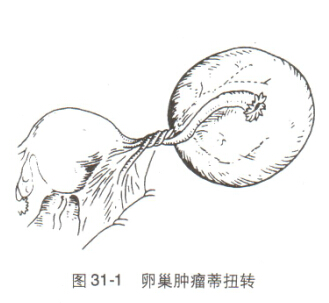

卵巢扭转是指卵巢及其输卵管附件在体内发生扭转。这是一种妇科急症,严重时可危及卵巢健康,甚至生命。症状

卵巢扭转的确切原因尚不清楚,但可能与以下因素有关:- 卵巢肿大或囊肿

卵巢扭转的治疗方法是立即手术。手术旨在解除扭转、恢复卵巢血供和切除受影响的组织。手术可以通过以下方式进行:- 腹腔镜手术:通过几个小切口插入腹腔镜和手术器械进行手术。